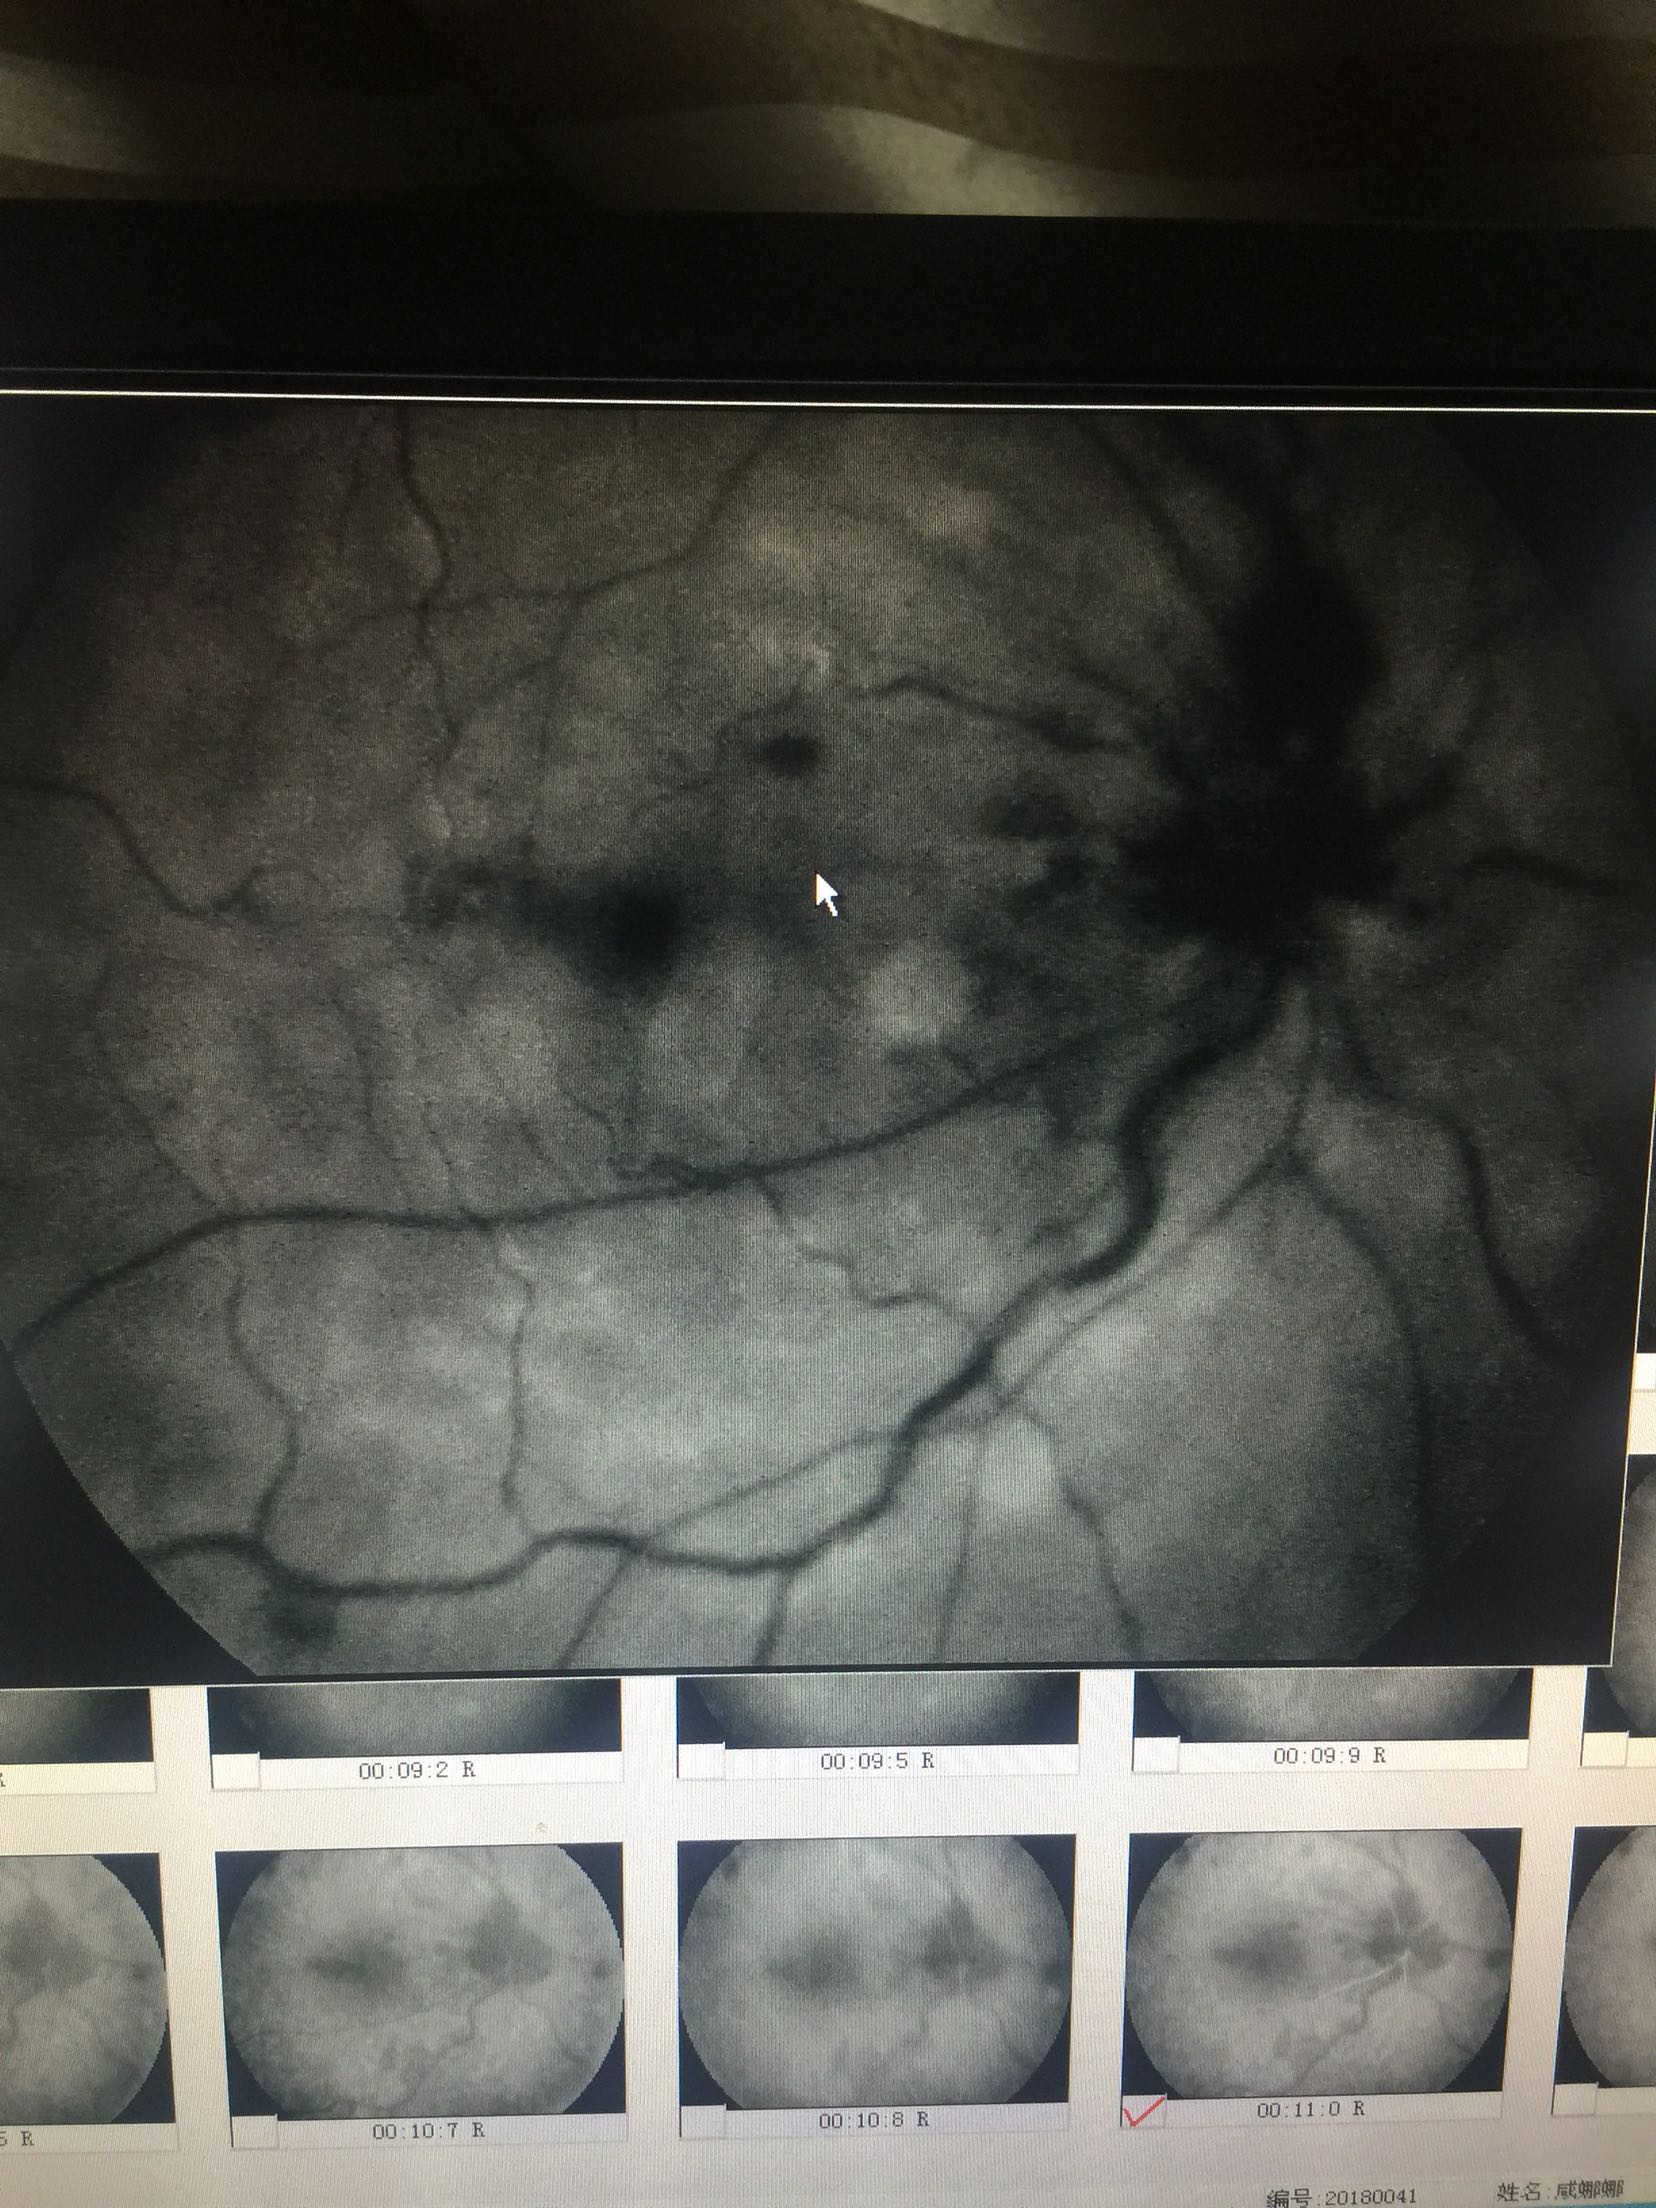

右眼:指数,左眼:0.15 双眼眼睑肤色正常,无红肿,结膜无充血,角膜透明,前房中深,瞳孔正大等圆,虹膜纹理清,晶体无浑浊,右眼眼底可见视盘出血水肿,边界不清,静脉迂曲扩张,黄斑区水肿出血,网膜散在片状出血,

右眼CRVO 扩张血管,营养神经治疗,眼底注射抗VEGF药

这种情况,很难有特别有效的预防手段,主要是规范生活习惯,避免劳累,饮食清淡。 眼底中央静脉阻塞引起的眼底出血,待出血吸收后,视力一般都会有进一步的提高的,但是要特别注意眼底新生血管增生的情况的,如果增生明显,会明显影响视力的,待出血吸收后,一定要做眼底造影明确的,必要时需要激光治疗的。